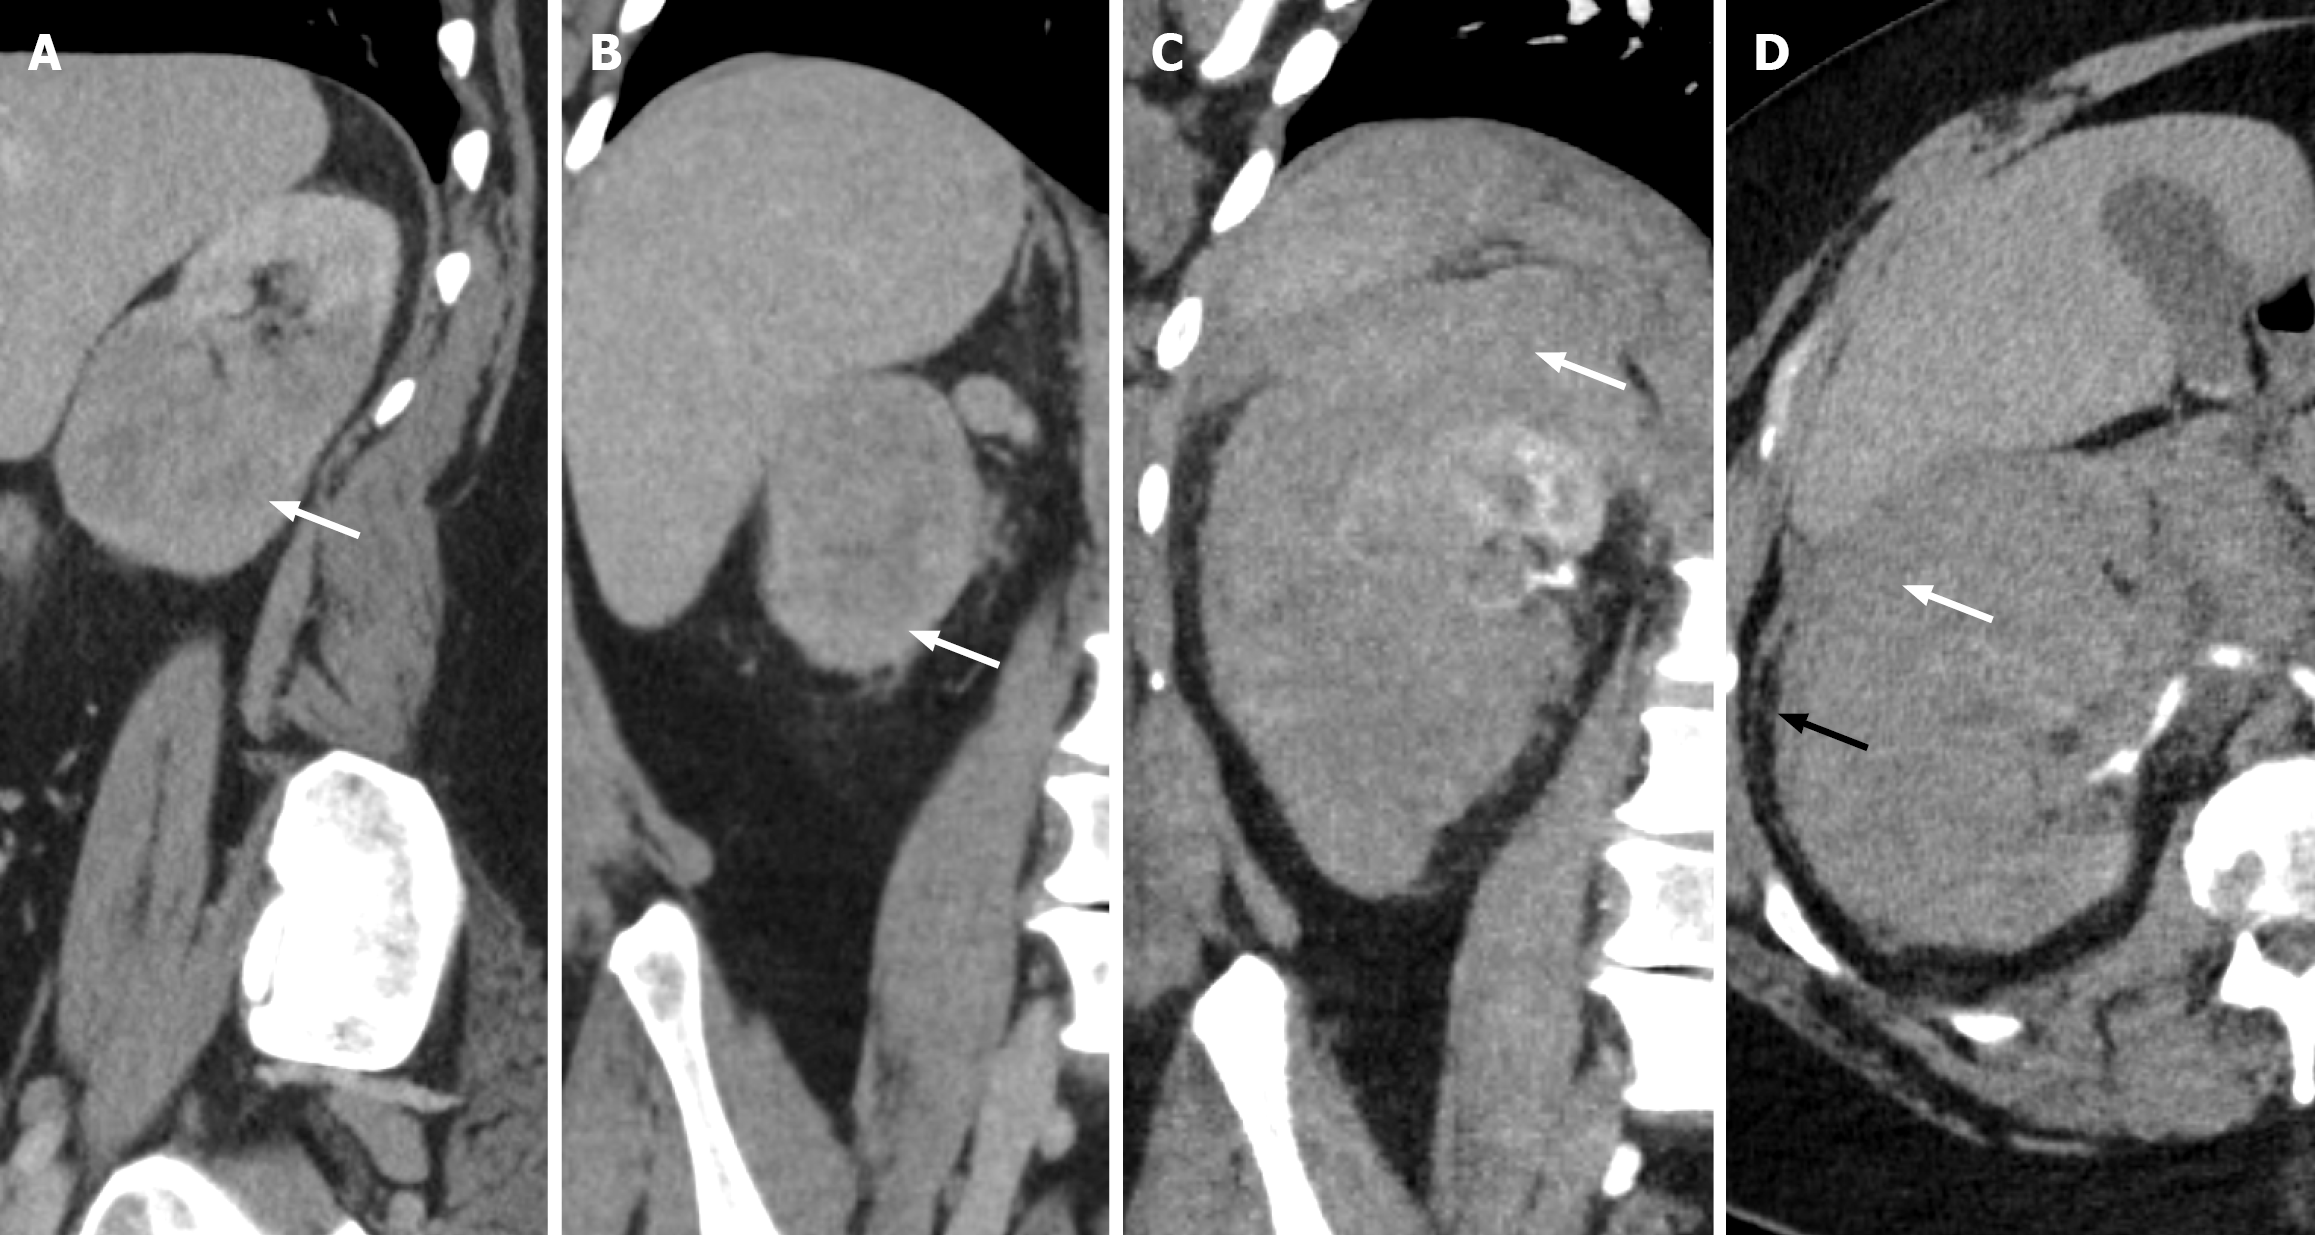

Figure 8 Spontaneous renal hemorrhage.

A and B: Sagittal (A) and (B) computed tomography of the right kidney demonstrating a homogenous hypoattenuating mass infiltrating the inferior portion of the right renal parenchyma, consistent with renal lymphoma (white arrow). A few months later, the patient presented with acute abdominal/right flank pain; C and D: Coronal (C) and (D) axial computed tomography demonstrating a hyperdense subcapsular collection consistent with spontaneous renal haemorrhage and subcapsular hematoma (white arrow) with slight extension into the perinephric space (black arrow).